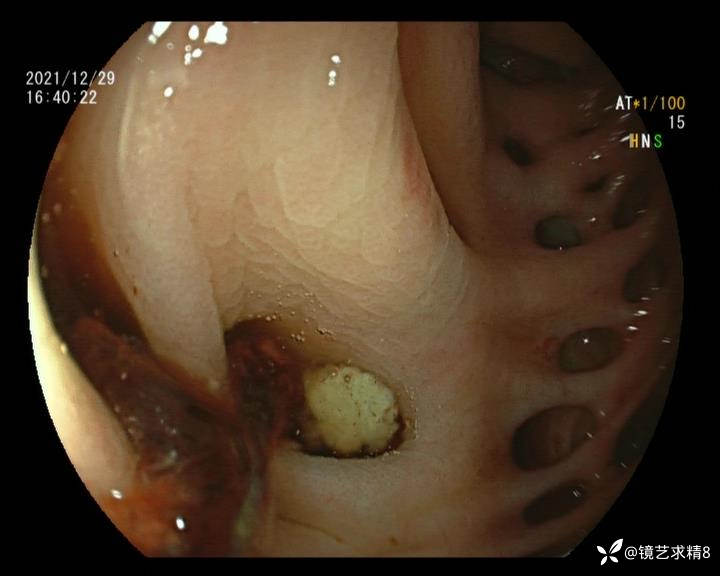

结肠内违建⥤结肠多发憩室☞续

小壮兵爱学习等 2人推荐看到手机存有2年前一个病例仅有的3张图片,因为没有更多的图片就只描述了多发憩室这个内容,没想到浏览量很快上万,很多都和我一样第一次见这么多憩室的结肠,就不得不想要把2年前所有的片子拷贝出来分享。该病例憩室合并外源性因素成为憩室出血的原因。后面附有代表性的全结肠图片。

患者以消化道出血入院,胃镜未见异常,肠镜进入乙状结肠就看到很多憩室,同时还看到肠腔用清肠药后移动下来1枚尖锐的枣核,这么多憩室,这个枣核扎入憩室的机会非常大,推测应该是掉入一坑🕳就算出来还会有很多坑🕳🕳🕳等着,掉入憩室内很容易刺破血管,这可能就是消化道出血的原因,继续前进可以看到有一些憩室内翻,还有一些息肉,问题来了,那么多憩室,犯罪分子是抓住了,它在那些憩室内作过案?到达回盲部后挨个冲洗,但憩室大小又不足以把镜头进入憩室内观察,针对有血块的憩室冲洗后可疑出血的以夹子闭合或套扎,取出枣核,如果有锥形透明帽可能钻入憩室精准电凝效果更好,若内镜下操作失败介入治疗成功率更高,经内镜下治疗后观察未再出血出院。